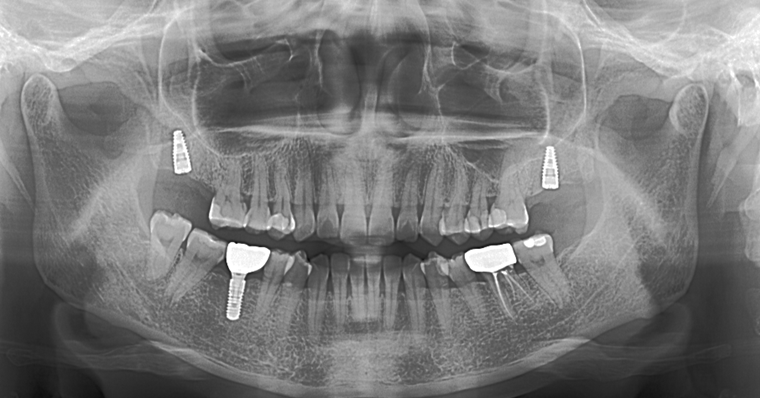

本次手术面向一名女性患者,需完成上颌左右两侧第二恒磨牙的种植手术。该区域毗邻上颌窦,且患者窦底位置偏低,手术核心难点在于精准操作、避免损伤上颌窦底。

观摩伊始,刘东辉医生先对患者基本情况、种植位点与数量、种植区域条件、植体选型、模拟植体植入等做了全面简要介绍,让学生们提前明晰病例核心要点。

随后,邵丹院长正式开展种植手术,全程操作规范、精准高效。在局部浸润麻醉注射环节,患者突发恶心呕吐不适。邵院长第一时间停止操作,耐心安抚患者情绪、主动转移其注意力,待患者不适缓解、状态平稳后,再继续推进手术。凭借娴熟的临床操作,两颗种植体精准植入预设位置,全程未损伤上颌窦底,手术圆满成功。